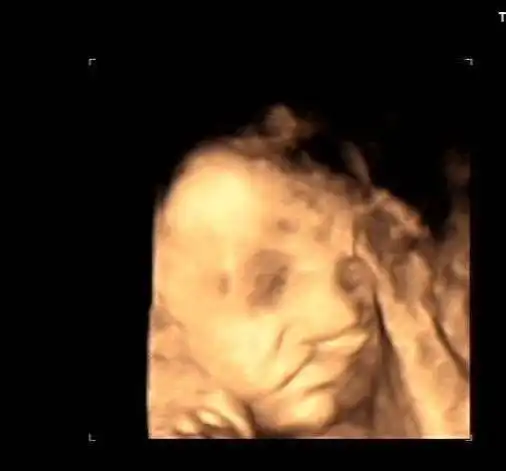

请各位宝妈帮我看一下这个四维是兔唇吗?

四维照片宝宝这样算兔唇吗

胎儿双侧唇裂四维成像图

是唇裂吗?有出生结果

遗憾!安真四维彩超筛查出一例胎宝宝"兔唇"

双胎宝妈21周做四维彩超,筛查出一名胎儿为"唇腭裂"